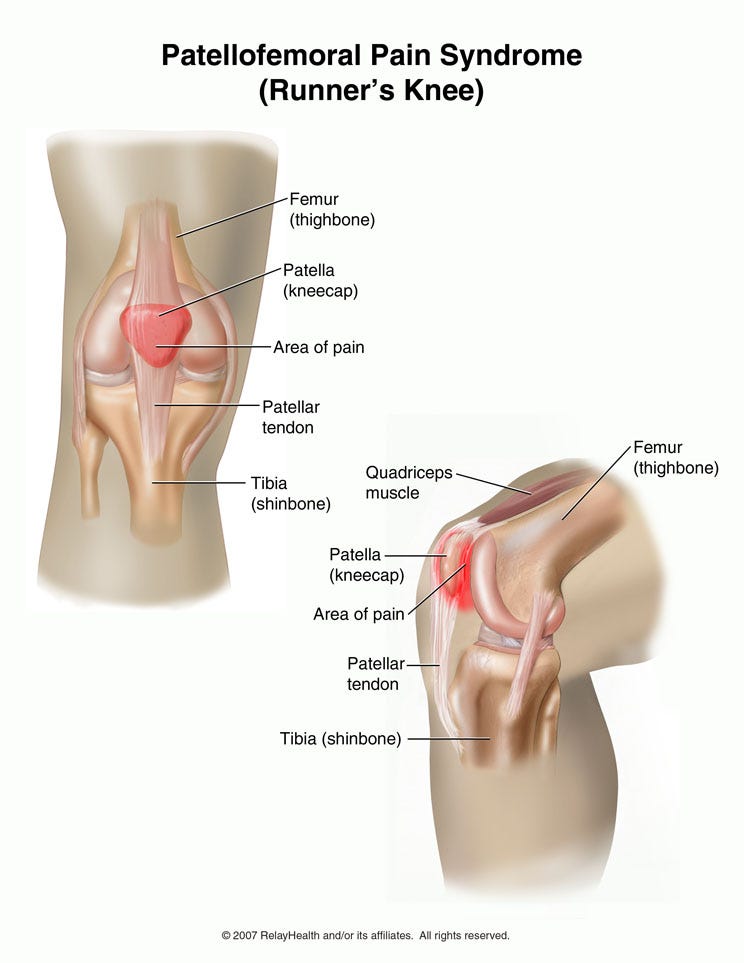

Where or Where Has My Patella Gone Direct Orthopedic Care 2024, Patella Kneecap Anatomy and Function 2024, Patellofemoral Pain Syndrome OrthoInfo AAOS 2024, The Patella Surface Anatomy Functions Dislocation 2024, Patella Wikipedia 2024, Patellar Fractures Broken Kneecap OrthoInfo AAOS 2024, Patellofemoral Joint Structure Function Conditions 2024, Patellofemoral Joint Physiopedia 2024, Patellar region Flashcards Quizlet 2024, Patella Injury Treatments Knee Surgeons Consultants Yorkshire 2024, Patella Anatomy function and clinical aspects Kenhub 2024, Patellar Tendonitis Jumper s Knee Johns Hopkins Medicine 2024, ITB vs Patellofemoral Pain Syndrome Symptoms Knee Pain In Runners 2024, Patellofemoral Pain Syndrome OrthoInfo AAOS 2024, Patella Anatomy function and clinical aspects Kenhub 2024, Patellar Tendonitis Jumpers Knee Symptoms Diagnosis Treatment 2024, Patellofemoral Pain Syndrome Rural Physio at Your Doorstep 2024, Patellar tendinitis Symptoms causes Mayo Clinic 2024, Patella Femoral Syndrome Montgomery Massage Therapy 2024, Jumper s Knee Symptoms in Kids Jumper s Knee Treatment 2024, Anatomy of Patella Bone and Spine 2024, Patellar Tendonitis Jumper s Knee Symptoms Causes Mount 2024, Anatomy Gruppo Bioimpianti 2024, Patellofemoral Pain Syndrome 2024, Patella Tendinopathy also known as Jumper s Knee Complete Physio 2024, Patellofemoral Pain Syndrome PFPS Symptoms Treatment 2024, Patellar Tendonitis 2024, Patellofemoral Joint Physiopedia 2024, How to avoid Runner s Knee . Forty two percent of all overuse 2024, Osgood Schlatter Disease Knee Pain OrthoInfo AAOS 2024, Tendinitis in the Knee 2024, Patella Kneecap Definition Location Anatomy Diagram 2024, Patellar Tendinopathy Rural Physio at Your Doorstep Physio Direct 2024, Knee Pain Location Chart SPORT Orthopedics Dallas and Frisco 2024, 10 Common Knee Injuries Diseases 2024.

Where or Where Has My Patella Gone Direct Orthopedic Care 2024, Patella Kneecap Anatomy and Function 2024, Patellofemoral Pain Syndrome OrthoInfo AAOS 2024, The Patella Surface Anatomy Functions Dislocation 2024, Patella Wikipedia 2024, Patellar Fractures Broken Kneecap OrthoInfo AAOS 2024, Patellofemoral Joint Structure Function Conditions 2024, Patellofemoral Joint Physiopedia 2024, Patellar region Flashcards Quizlet 2024, Patella Injury Treatments Knee Surgeons Consultants Yorkshire 2024, Patella Anatomy function and clinical aspects Kenhub 2024, Patellar Tendonitis Jumper s Knee Johns Hopkins Medicine 2024, ITB vs Patellofemoral Pain Syndrome Symptoms Knee Pain In Runners 2024, Patellofemoral Pain Syndrome OrthoInfo AAOS 2024, Patella Anatomy function and clinical aspects Kenhub 2024, Patellar Tendonitis Jumpers Knee Symptoms Diagnosis Treatment 2024, Patellofemoral Pain Syndrome Rural Physio at Your Doorstep 2024, Patellar tendinitis Symptoms causes Mayo Clinic 2024, Patella Femoral Syndrome Montgomery Massage Therapy 2024, Jumper s Knee Symptoms in Kids Jumper s Knee Treatment 2024, Anatomy of Patella Bone and Spine 2024, Patellar Tendonitis Jumper s Knee Symptoms Causes Mount 2024, Anatomy Gruppo Bioimpianti 2024, Patellofemoral Pain Syndrome 2024, Patella Tendinopathy also known as Jumper s Knee Complete Physio 2024, Patellofemoral Pain Syndrome PFPS Symptoms Treatment 2024, Patellar Tendonitis 2024, Patellofemoral Joint Physiopedia 2024, How to avoid Runner s Knee . Forty two percent of all overuse 2024, Osgood Schlatter Disease Knee Pain OrthoInfo AAOS 2024, Tendinitis in the Knee 2024, Patella Kneecap Definition Location Anatomy Diagram 2024, Patellar Tendinopathy Rural Physio at Your Doorstep Physio Direct 2024, Knee Pain Location Chart SPORT Orthopedics Dallas and Frisco 2024, 10 Common Knee Injuries Diseases 2024.